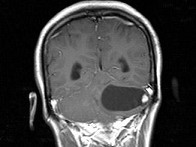

女,27岁,头昏、行走不稳1个月,PE:指鼻试验(+),Romberg氏征(+),根据所提供图像,最可能的诊断()

A.左小脑脓肿

B.左小脑血管母细胞瘤

C.左小脑星形细胞瘤

D.左小脑胶质细胞瘤

E.左小脑转移瘤

女,27岁,头昏、行走不稳1个月,PE:指鼻试验(+),Romberg氏征(+)

[单选题]女,27岁,头昏、行走不稳1个月,PE:指鼻试验(+),Romberg氏征(+),根据所提供图像,最可能的诊断()A . 左小脑脓肿B . 左小脑血管母细胞瘤C . 左小脑星形细胞瘤D . 左小脑胶质细胞瘤E . 左小脑转移瘤